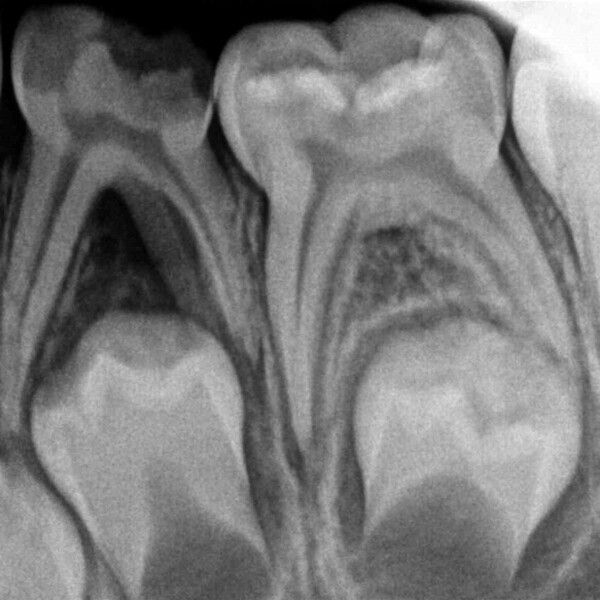

Cas 3 (Figs. 10 à 13)

Ce patient âgé de 7 ans présentait une douleur légère depuis plusieurs jours. L’examen a montré une lésion cavitaire étendue et profonde dans la première molaire temporaire inférieure gauche. La gencive ne présentait aucun gonflement, mais la dent était douloureuse à la percussion. La radiographie a confirmé la gravité de la carie, mais n’a révélé aucun signe correspondant à une modification de l’os environnant. Une pulpectomie était le traitement de choix. Le diagnostic de nécrose pulpaire a été confirmé après la préparation de la cavité d’accès et l’identification de trois canaux qui ont alors été complètement négociés.Lors d’un second rendez-vous, 15 jours plus tard, la dent était totalement asymptomatique et elle a été restaurée au moyen d’une couronne en acier inoxydable. À la visite de suivi à 36 mois, la dent présentait une fonction normale et était totalement saine.